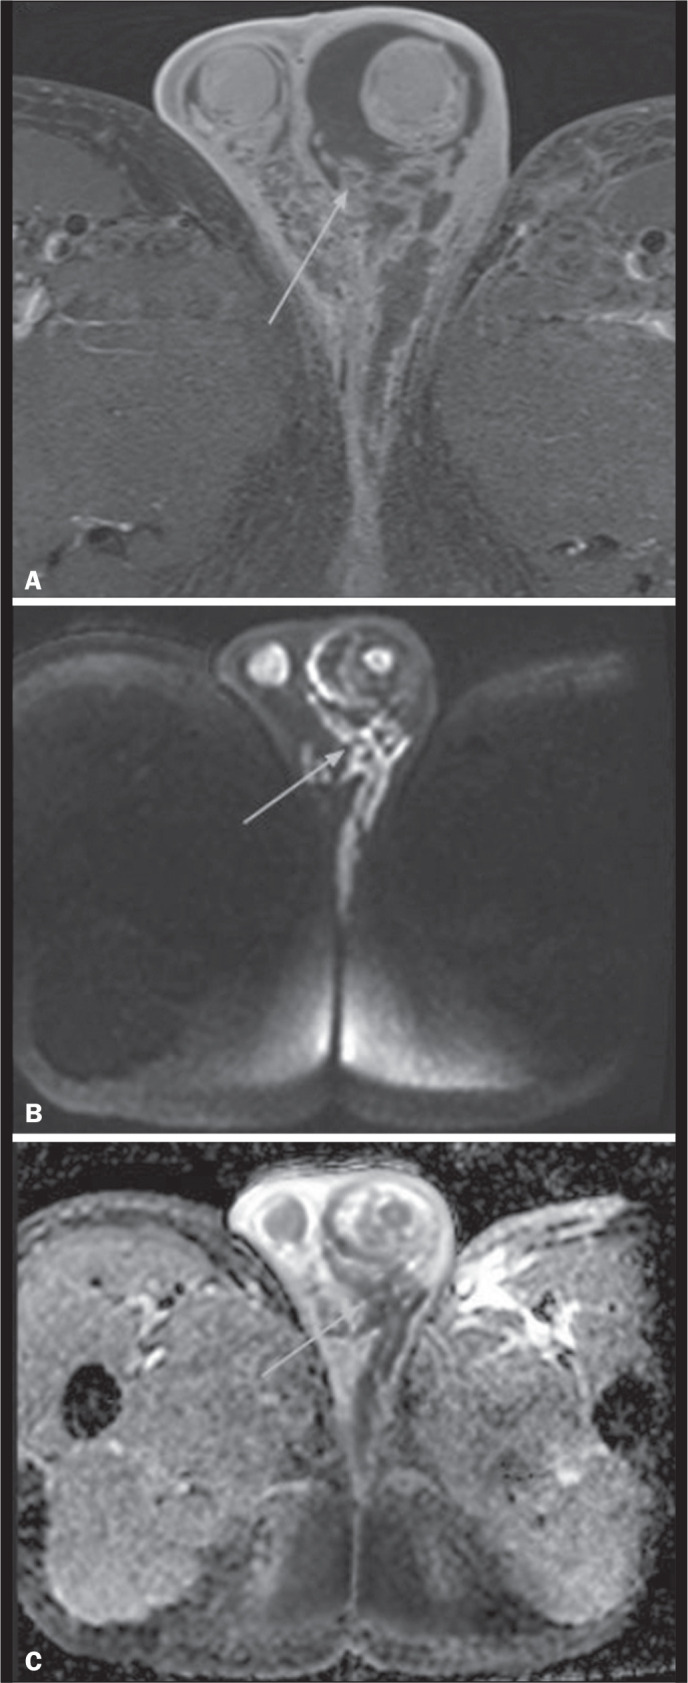

Magnetic resonance imaging is an essential tool for the assessment of the scrotum, particularly in cases with inconclusive ultrasound findings. It has a great capacity to differentiate between intratesticular and extratesticular lesions, as well as between neoplastic and non-neoplastic lesions. By providing an accurate characterization of lesions, magnetic resonance imaging plays a crucial role in preoperative tumor staging and decision-making. This pictorial essay highlights the key non-neoplastic and neoplastic testicular pathologies, as evaluated by magnetic resonance imaging. The recognition of these pathologies underscores the role the radiologists play in the care of patients with scrotal lesions, by providing an appropriate evaluation of the relevant imaging characteristics.